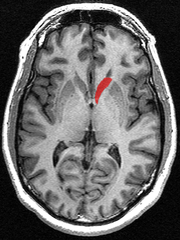

The caudate nuclei are located near the center of the brain, sitting astride the thalamus. There is a caudate nucleus within each hemisphere of the brain. Individually, they resemble a C-shape structure with a wider "head" (caput in Latin) at the front, tapering to a "body" (corpus) and a "tail" (cauda). Sometimes a part of the caudate nucleus is referred to as the "knee" (genu).[5]

The head and body of the caudate nucleus form part of the floor of the anterior horn of the lateral ventricle. After the body travels briefly towards the back of the head, the tail curves back toward the anterior, forming the roof of the inferior horn of the lateral ventricle. This means that a coronal (on a plane parallel to the face) section that cuts through the tail will also cross the body and head of the caudate nucleus.